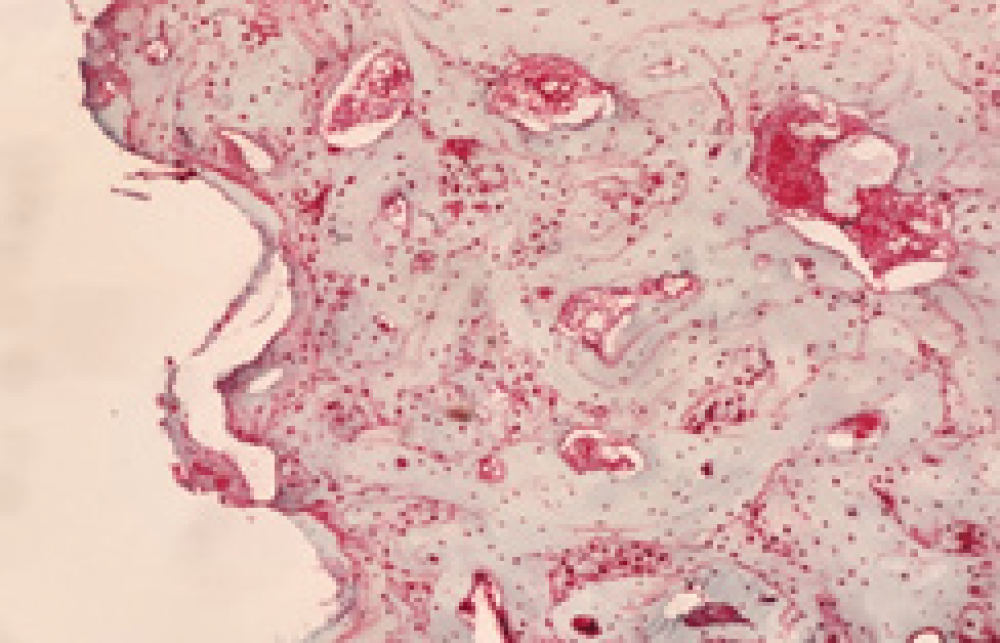

No necrosis formation is observed during the experiment. Although the degree of fibrosis was lower in the control group, the difference between it and the experimental group was not found to be statistically significant. No difference was observed regarding the occurrence of inflammation depending on the use of SSRIs (Figure 2a, 2b, 2c, 2d).

Figure 2. a: Bone-implant junction observed in the cortical bone in the experimental group, H&E, 40X, b: Lamellar bone remodeling on the bone-implant surface advancing towards the medullary area in the experimental group, H&E, 100X, c: Lamellar bone remodeling on the bone-implant surface advancing towards the medullary area in the experimental group, H&E, 200X, d: Bone marrow distance on the right side in the experimental group, bone remodeling in the implant threads on the left side, H&E, 100X (8th week)

Figure 3. Cytoplasmic and nuclear granular staining was observed in osteoclasts, osteoblasts, and osteocytes. osteopontin, 200x